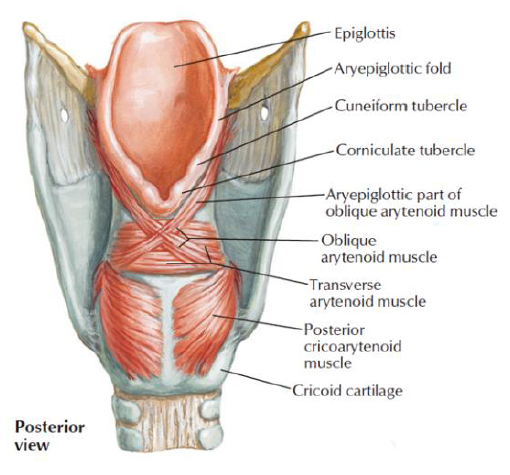

Muscle

關閉 Epiglotticus

- Thyroepiglotticus m

- Aryepiglotticus

Vocal fold

Motor: Recurrent laryngeal n.

- Arytenoid m.

- Transverse fiber / Oblique fiber

- Vocal fold adduction

- Post. cricoarytenoid

- Vocal fold abduction

- Lateral cricoarytenoid m.

- Vocal fold adduction

- Thyroarytenoid m.

- Arytenoid cartilage 往前

Motor: External laryngeal n.

- Cricothyroid m.